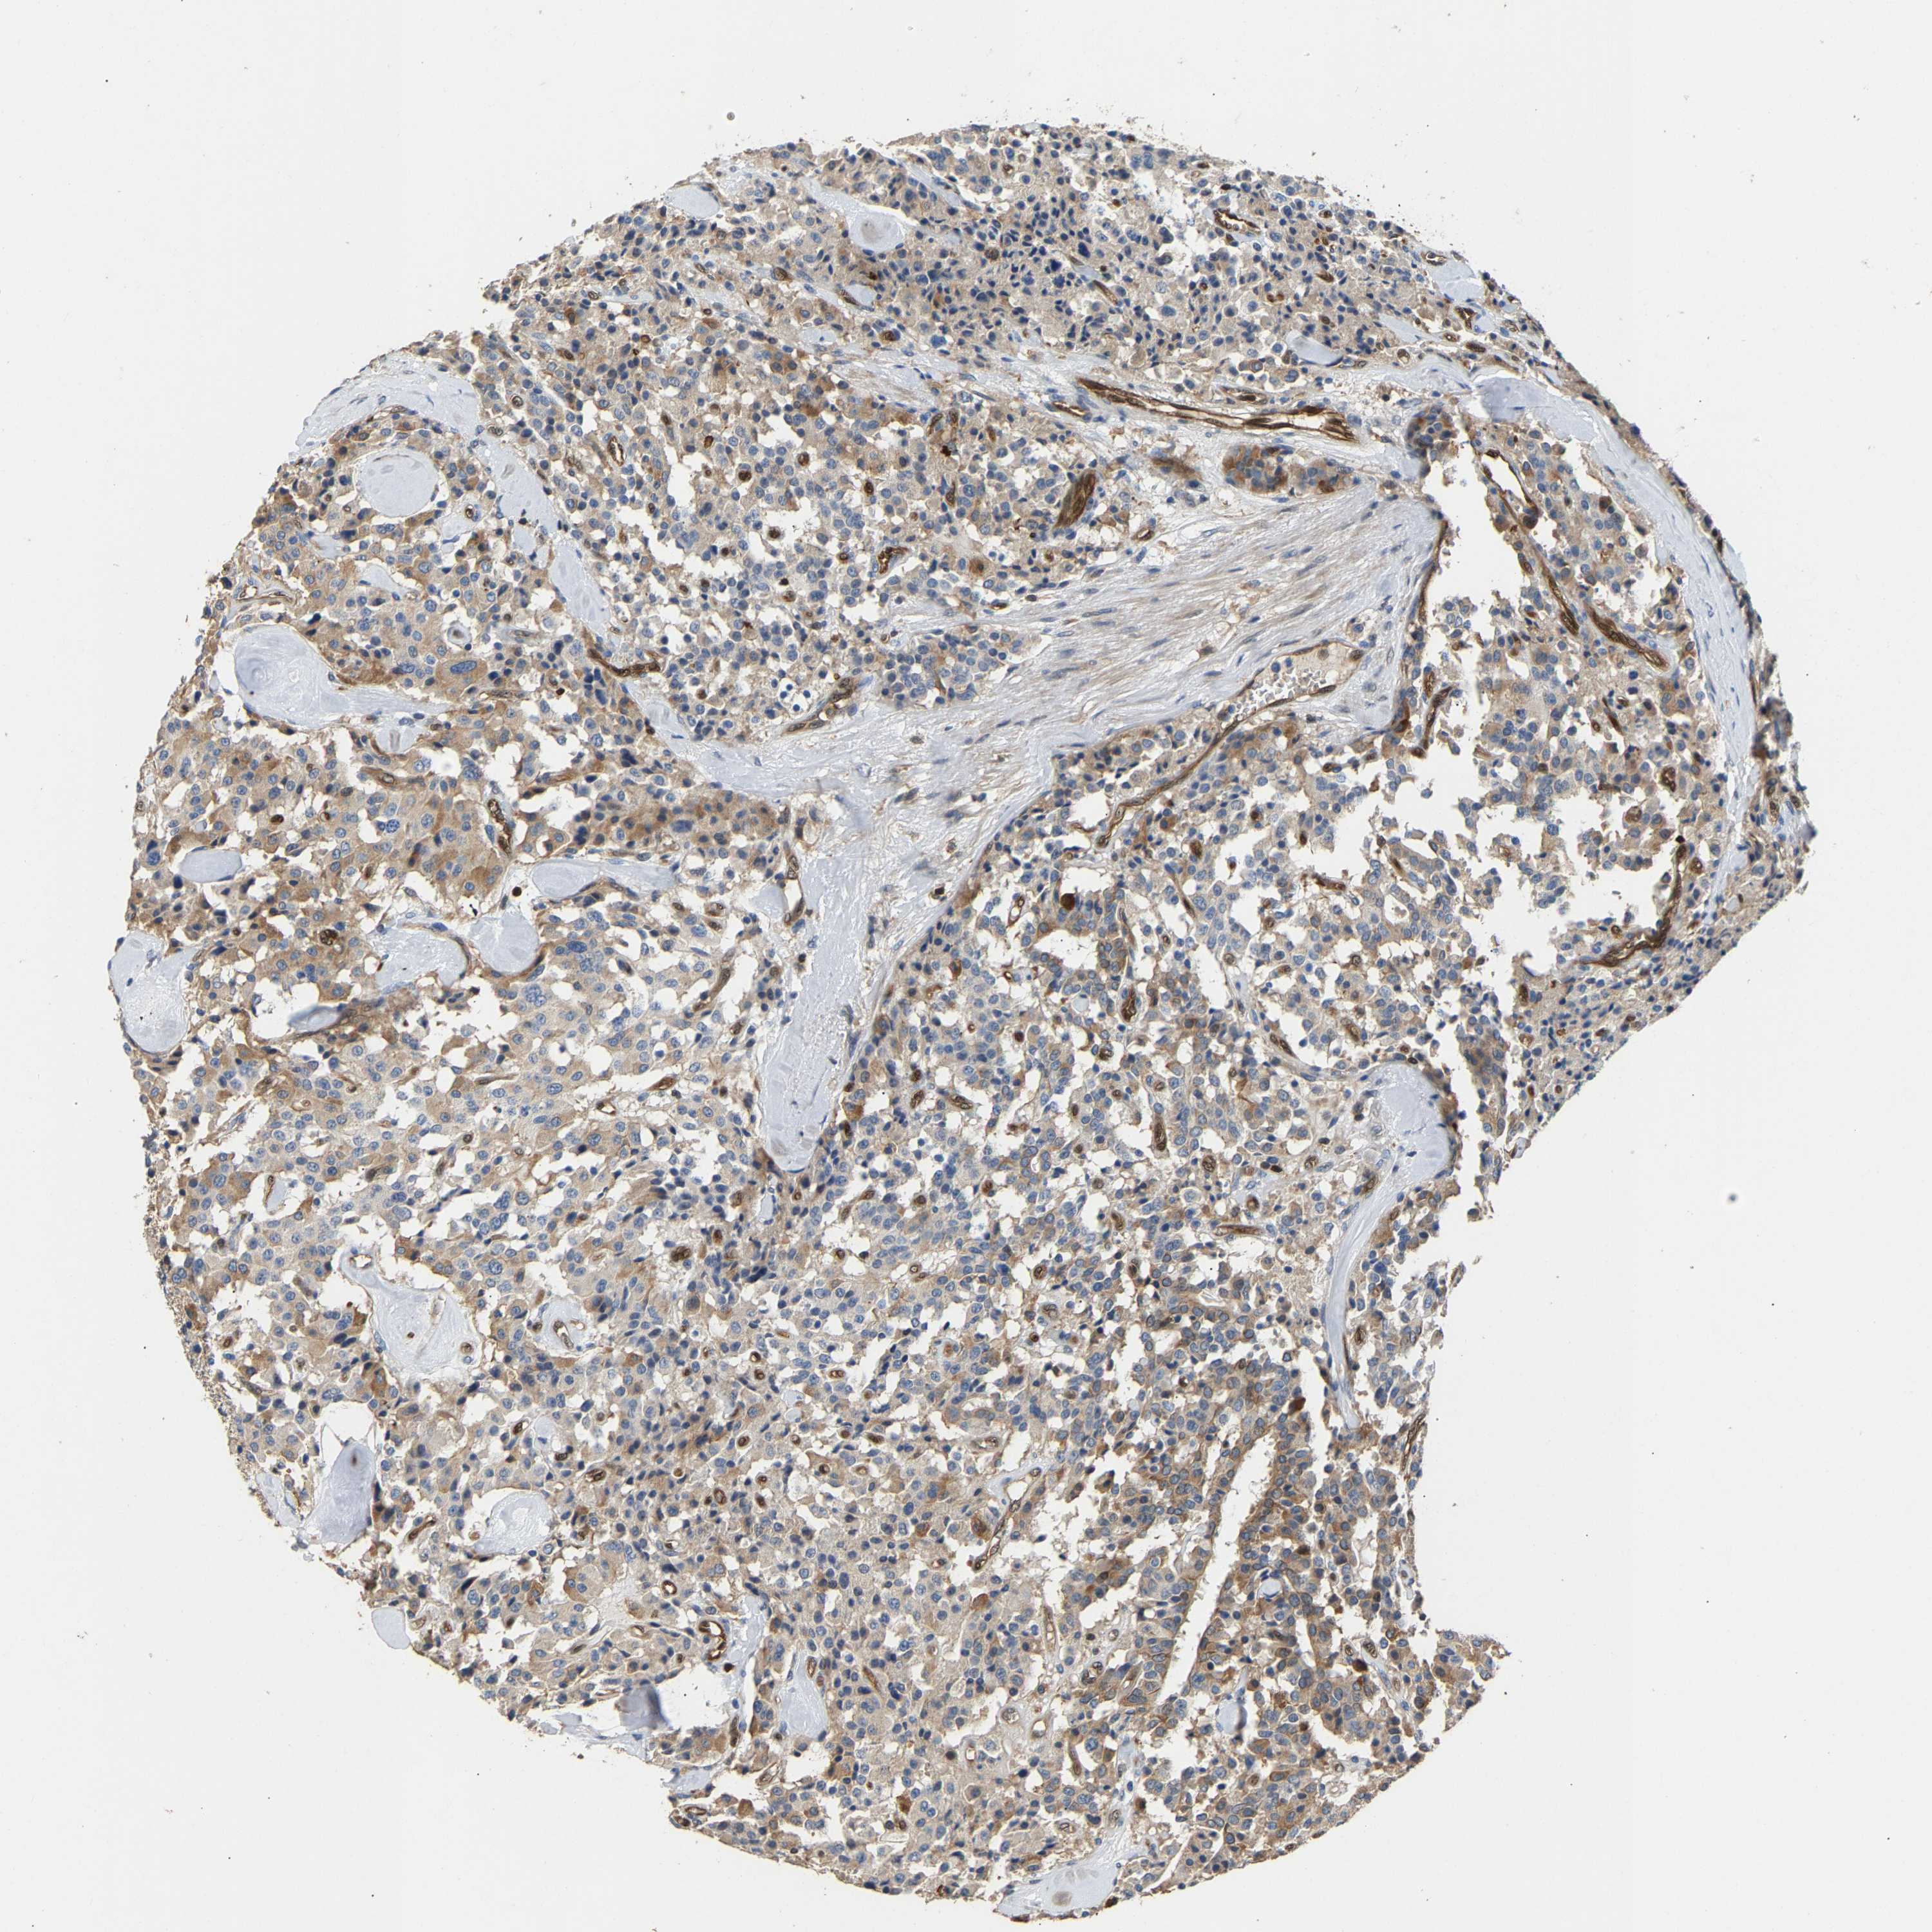

CARCINOID - Protein expressioni

A mouse-over function shows sample information and annotation data. Click on an image to view it in a full screen mode. Samples can be filtered based on level of antibody staining by selecting one or several of the following categories: high, medium, low and not detected. The assay and annotation is described here.

Antibody stainingi

Antibody staining in the annotated cell types in the current human tissue is reported as not detected, low, medium, or high, based on conventional immunohistochemistry profiling in selected tissues. This score is based on the combination of the staining intensity and fraction of stained cells.

Each image is clickable and will lead to virtual microscopy that enables deeper exploration of all samples and also displays staining intensity scores, fraction scores and subcellular localization as well as patient and tissue information for each sample.

Antibody HPA020266

Antibody HPA020268

Staining

High

Medium

Low

Not detected

Intensity

Strong

Moderate

Weak

Negative

Quantity

>75%

75%-25%

<25%

None

Location

Nuclear

Cytoplasmic/membranous

Cytoplasmic/membranous,nuclear

Carcinoid, malignant, NOS

Carcinoma, NOS